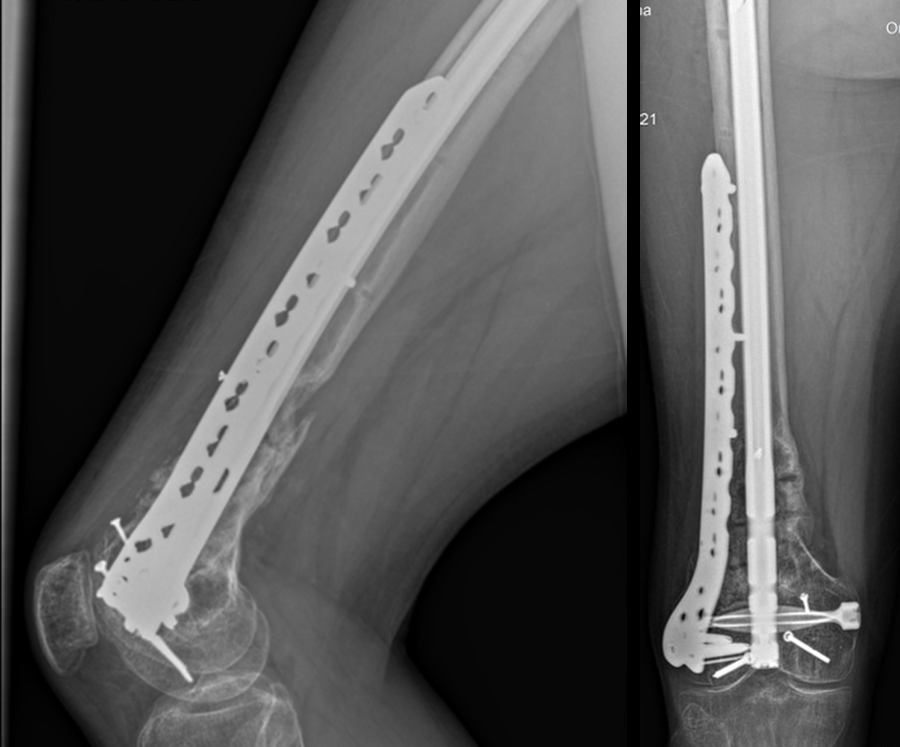

At the 6-month follow-up (Fig 14), the patient was able to WBAT on the right lower extremity. He had some ankle pain and a ROM of 0–125 in his right knee. The patient was able to walk without any assistance device.

At the 9-month follow-up (Fig 15), the patient reported nominal knee pain, but more pain in his ankles. The patient had returned to work. He was not undertaking any heavy lifting but was driving the truck and supervising the team. Overall, the patient was happy with the current outcome of surgery.